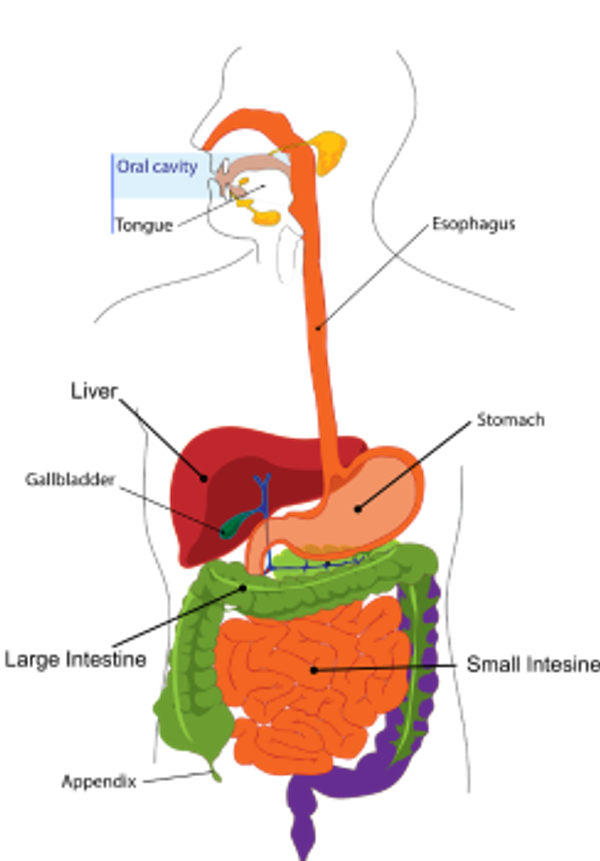

Nachdem die Gallenflüssigkeit in der Leber produziert wurde, wird sie in der Gallenblase - der vesica fellea - gespeichert, einem birnenförmigen Hohlorgan, das sich rechts oben in der Bauchhöhle unterhalb der Leber befindet. In der Gallenblase wird die Gallenflüssigkeit eingedickt, indem ihr Wasser entzogen wird. Wenn fetthaltige Nahrung in den Magen gelangt, reagieren die Muskeln der Gallenblase und ziehen sich zusammen, wodurch die Galle durch den Gallengang in den Zwölffingerdarm fließt. Dieser Prozess wird durch das Hormon Cholecystokinin gesteuert. Die in der Gallenflüssigkeit enthaltenen Gallensalze spalten dann die Fette in winzige Tröpfchen auf. Die Menge der freigesetzten Gallenflüssigkeit ist abhängig von der Menge des Fetts.